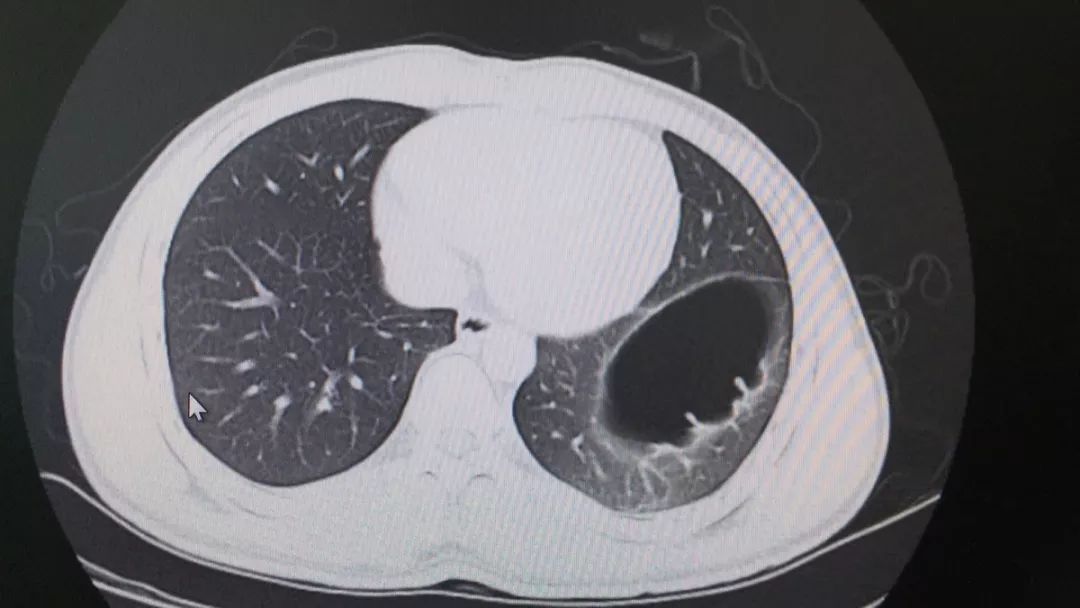

一例左侧膈疝误诊为气胸 [病例帖]

膈疝还是膈膨升 [病例帖]